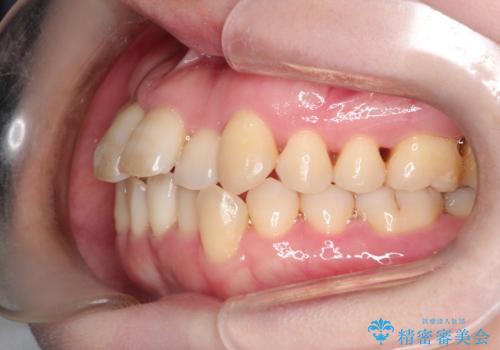

【インビザライン】ずれた前歯の噛み合わせをなおしたい

- 前歯の噛み合わせが悪いことを主訴に来院されました。

歯周病も併発していたため、歯牙への負担が少なくなるように治療計画をたて、インビザラインにて治療を完了しました。

矯正開始前に半年間、歯周治療を行ってからインビザラインを装着しています。